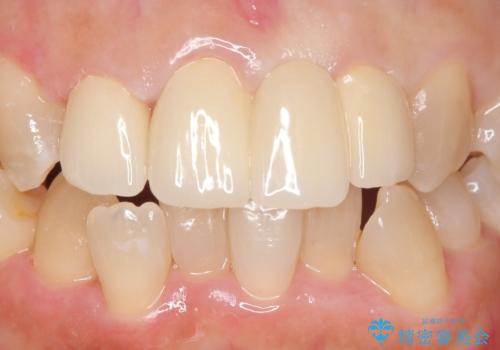

オールセラミッククラウン 変色した前歯を白く綺麗な歯へ

- 前歯の歯並びや色が気になるといらっしゃった方の症例です。

前歯4本をオールセラミッククラウンで補綴することで、歯の並びや色の改善を行いました。

今回用いたオールセラミッククラウンはジルコニアフレームという白い素材の上にセラミックを盛っているため、審美性が非常に高いのが特徴です。